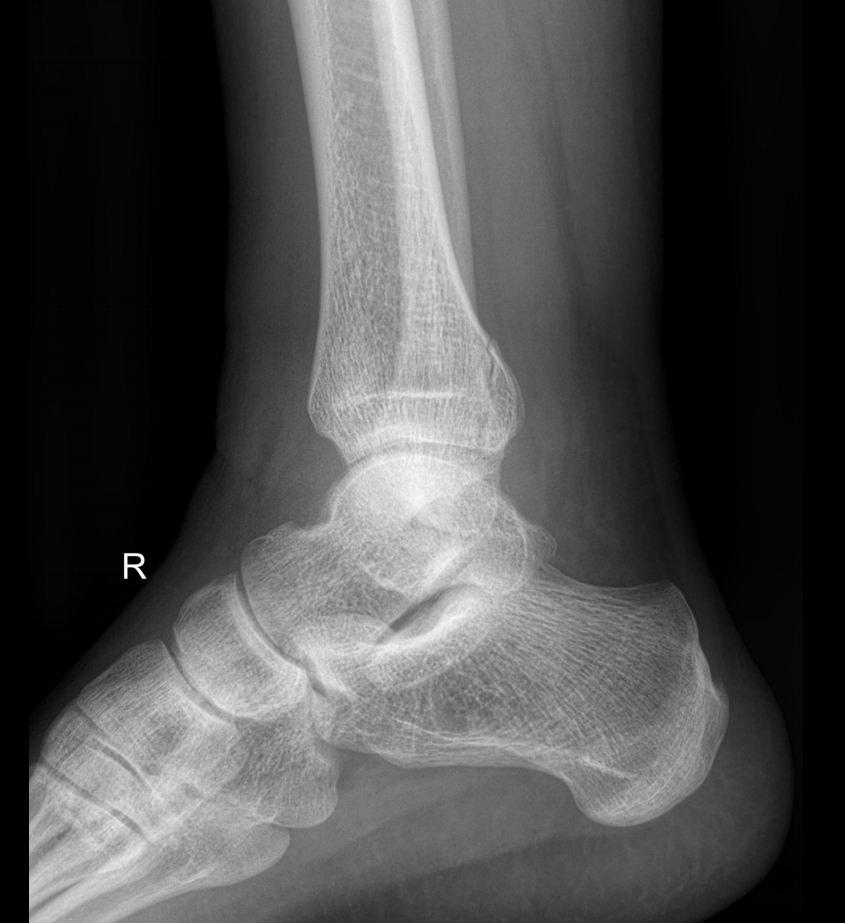

Голеностопные суставы отличаются сложным строением, в позволяющим стопе вращаться, сгибаться и разгибаться почти на 90о. Благодаря этому тело свободно перемещается в пространстве, меняет свое положение, поднимает собственный вес и дополнительный груз. Травмы голеностопных суставов встречаются также часто, как и хронические заболевания.

В качестве скринингового, а зачастую и единственного метода диагностики голеностопных суставов обычно используют рентген. Его вполне достаточно для визуализации внутреннего строения сустава и патологических изменений в нем. А цифровая нагрузка цифрового оборудования последнего поколения  несет минимум излучения и позволяет безопасно делать несколько снимков подряд.

Обследование обоих суставов с помощью рентгена помогает подтвердить диагноз, сравнить проявления на разных ногах, установить стадию заболевания, выбрать тактику лечения и определить его эффективность при следующих патологиях:

• Переломы и вывихи;

• Врожденные аномалии;

• Онкология;

• Дегенеративно-дистрофические заболевания.

• Изменения, произошедшие в костной ткани элементов суставов ― разрежение, некроз, озлокачествление, склерозирование;

• Нарушение четкости контуров костных образований;

• Перелом, его местоположение, смещение отломков;

• Состояние суставных щелей ― сужение, расширение, скопление жидкости, обызвествление капсулы;

• Конгруэнтность суставных поверхностей или вывих;

• Состояние мягких тканей ― отеки, инородные тела.